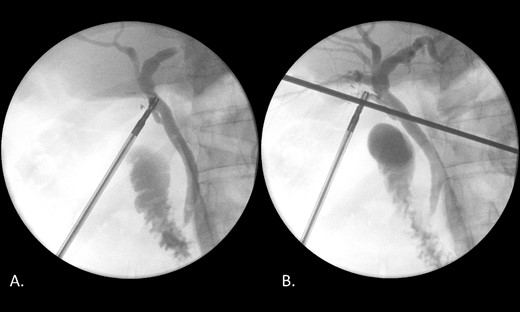

Endoscopic retrograde cholangiopancreatography (ERCP) was performed on day three of admission. Following CBD cannulation and sphincterotomy, balloon trawl of the duct was performed yielding a large volume of chalky, granular material with detritus and stones; confirming a diagnosis of LBS (Fig. 3). A stent however could not be placed as the gravelly material blocked the channel of the endoscope. Therefore, the obstructing calculus in the distal CBD was not obviously removed hence the recommendation was for intraoperative cholangiogram (IOC) to be performed at laparoscopic cholecystectomy to confirm if a filling defect remained in keeping with a calculus.

Intraprocedural images during ERCP demonstrating chalky limy bile.